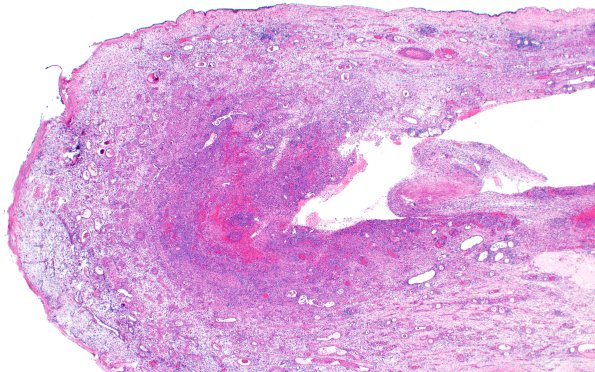

6B2 Nasal glioma (Case 6) H&E 2X

The surgical specimen as a whole mount with a discrete border and variegated content. (H&E)